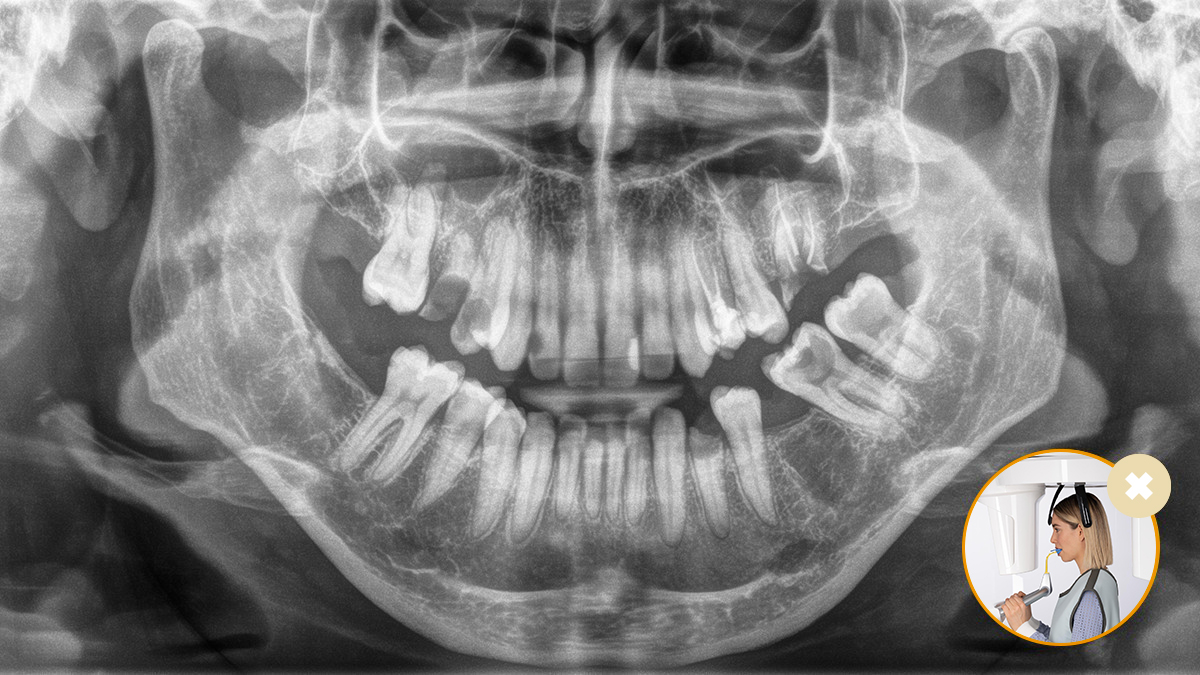

El resultado: Escaneos precisos gracias al bloque de mordida oclusal